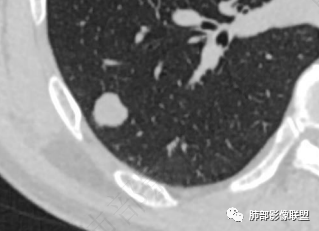

男,51。右肺下叶孤立实性结节,边界清,边缘少许磨玻璃,周围气肿带,浅分叶,平扫内见点状低密度,强化不明显。考虑良性结节,错构瘤>炎性肉芽肿鉴别腺癌。

右下叶胸膜下结节,轻分叶,结节内可见低密度区,CT值一83Hu,结节周围见空气新月征(黑边征),结节膨胀性生长,收缩力差,轻度强化,体检发现,综合分析,考虑错构瘤,但多个层面显示结节周围有边缘清楚的磨玻璃影,不知是否与层厚有关,有似清非清的感受,鉴别排除一下低分化腺癌

感觉磨玻璃影是容积效应

看到视频,是容积效应

那错构瘤的可能性就较大了

此病例中结节,与支气管无关系,边缘清晰,形态规则,缺乏张力,未见典型的分叶及毛刺,病灶周围磨玻璃为部分容积效应所致,肺门纵隔未见肿大淋巴结,良性病变可能性较大,肺部的良性肿瘤中,最常见的是错构瘤,其次是硬化性肺细胞瘤(PSP),第三是孤立性纤维性肿瘤(SFT)。

常表面光滑,可有浅分叶或无分叶,无毛刺,对周围肺组织无牵拉;常挂枝头(挂在肺动脉枝头上),很少到达胸膜。出现脂肪成分,或者典型的爆米花样钙化几乎可以确诊,软骨型错构瘤因软骨组织多,强化弱。平滑肌型错构瘤增强有一定强化。病灶周围边界清楚,常有很低密度的黑晕。